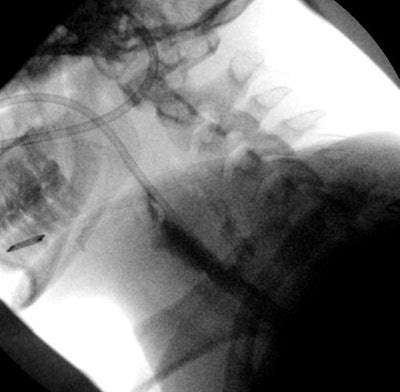

"Even if you see an object on x-ray, you can't necessarily assume you're seeing the whole thing," he said. "Complex objects like fidget spinners have parts that show up on radiography and parts that don't, and in this case, the jagged plastic part that did not show is what caused complications."

A woman in her late teens with a "complex mental health history including depression and eating disorder" swallowed parts of a fidget spinner broken into three pieces, Otjen and colleagues wrote. X-ray and endoscopic evaluation confirmed the presence of parts of the object in the esophagus; they were taken out via rigid endoscopy.

Removing the toy proved challenging due to the fact that parts of it were impinging the esophagus and needed to be rotated. Follow-up x-ray three days later showed retropharyngeal gas, which prompted an additional week of intravenous feeding for the patient. Other parts of the toy passed normally some days later.

"Because the object was four times larger than the normal esophageal lumen with jagged edges and showed no movement with nonsurgical treatment, injury was likely prior to removal," the researchers wrote.